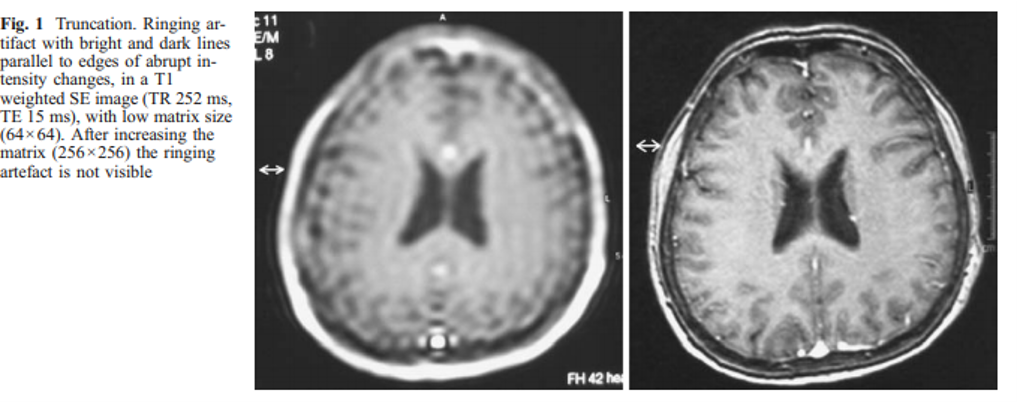

aliasing

also called Moire fringe artifact, commonly seen in GRE sequences and is a result of alternating constructive and destructive interference

Moire fringe artifact is commonly associated with what sequence?

GRE